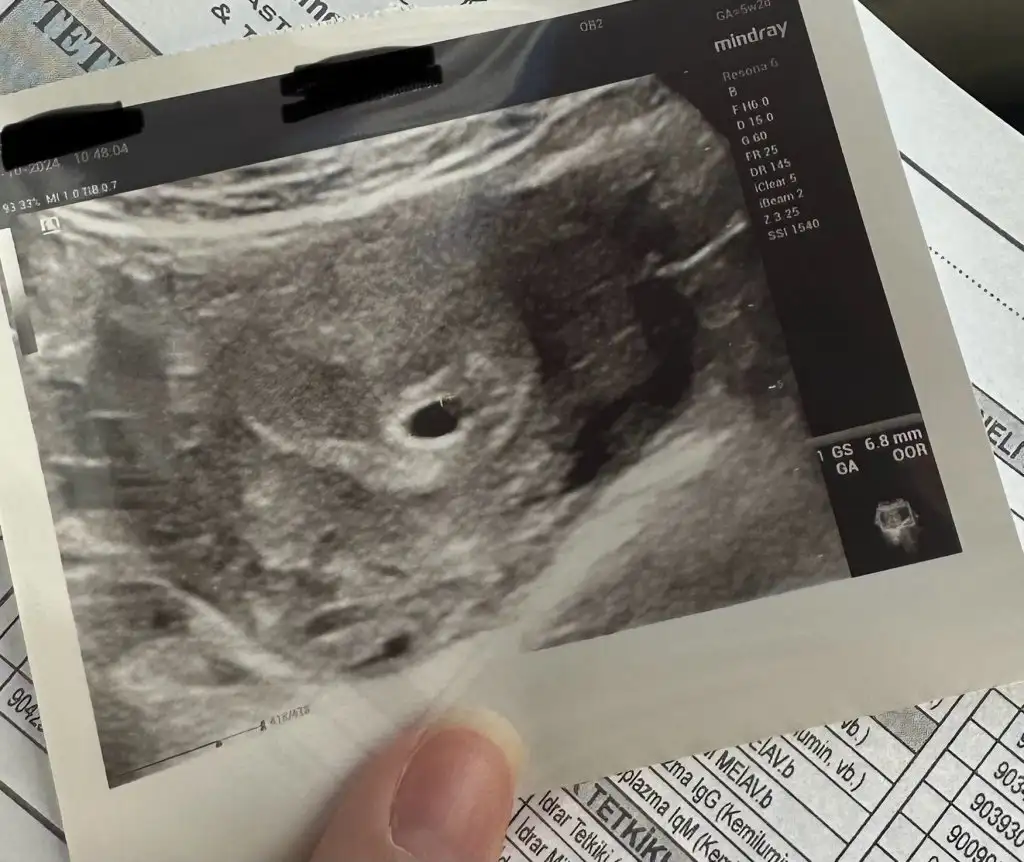

Hayırlı olsunKızlar bugün ilk kez kontrole gittim . Kese bu şekil göründü normal mi . 5+2 son adet tarihine göre . Yorumlayabilir misiniz. 2 hafta sonraya randevu verdi kalp atışı için

Teşekkür ederim sizede hayırlı olsun Pek açıklayıcı değildi. Kalp atışı duymadan kimseye söylemeyin dediHayırlı olsunbenim de ilk gebeliğim 5+1 de çağırdı doktorum gidince göreceğiz inşallah keseyi. Doktorunuz normal demiştir diye düşündüm